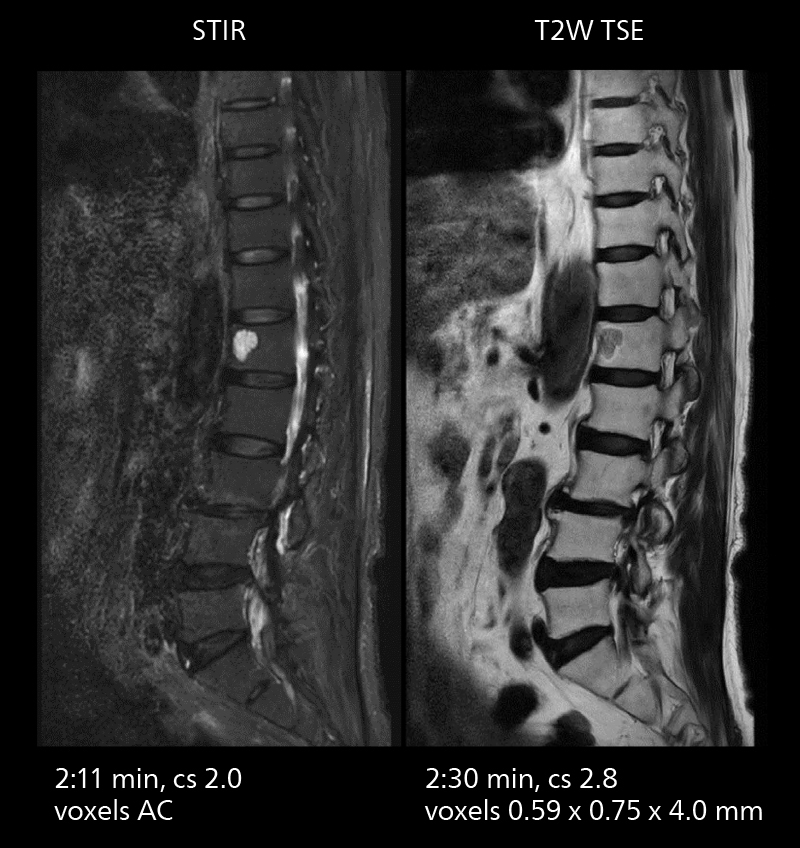

Crisp images are obtained with high resolution and short scan times using Elition X. A cyst can be seen.